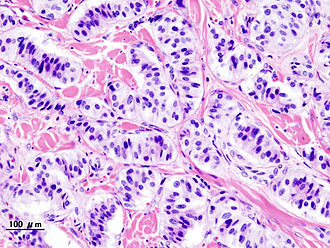

Pancreatic neuroendocrine tumour (insulinoma). H&E stain. | |

| LM | nests of cells or cords, stippled chromatin, moderate quantity of cytoplasm, +/-hyaline globules |

Features:

- Nests of cells or cords.

- Stippled chromatin - key feature.

- Moderate cytoplasm.

- +/-Hyaline globules.

The sections show pancreas with a large well-circumscribed tumour that centrally has a large cyst-like cavity. The tumour cells have moderate pale grey cytoplasm and round nuclei with salt and pepper chromatin. The tumour cells are arranged in cords and nests. No cholesterol clefts are readily apparent. No hyaline globules are identified. No papillary structures are apparent.

No necrosis is identified. No degenerative changes are apparent. Mitotic activity is seen focally. There are 2 mitoses per 10 high power fields, were one high power field has an area of 0.2376 mm*mm.